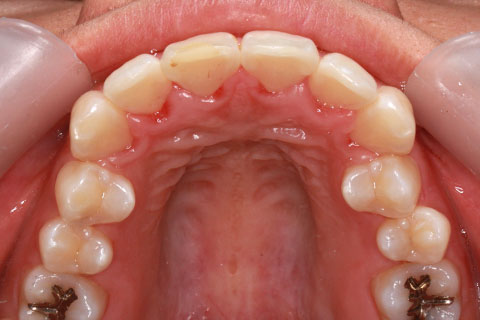

治療前

治療中(開始直後)

治療中(開始半年後)

治療後

- 年齢・性別

- 25歳女性

- 治療期間

- 2年0ヶ月

- 抜歯

- 上下4番抜歯

- 治療費

- 110万円

- 治療内容

- 施術の副作用(リスク)

- 表側矯正と比較して、力学的な操作性が複雑なため、ボーイングエフェクトを起こしやすい。